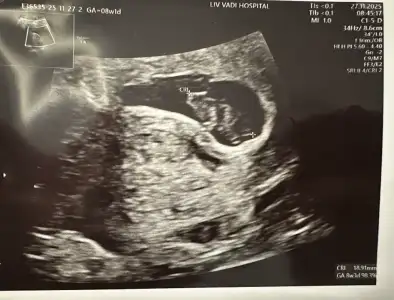

Ben de bir tahmin alabilir miyim minik kurbağam için :) 8+4 idi burada. Biz anne-baba olarak erkek hissediyoruz ama etrafımızdaki herkes kız hissediyor 🫠